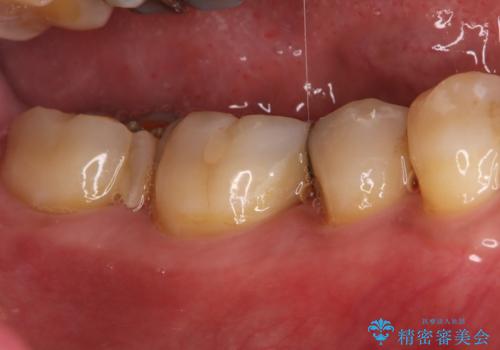

銀歯からセラミックへ。右上奥歯の精密根管治療と審美修復

担当医 河口智英